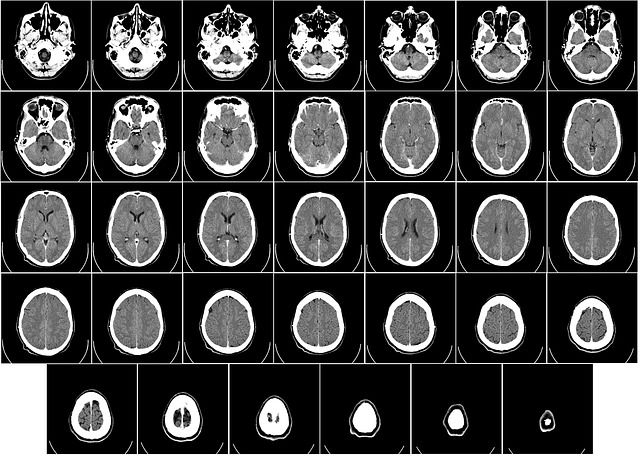

los medios más comunes utilizados por esta área de la medicina son los rayos x,

utilizando distintos métodos como fluoroscopias, mastografías o tomografías

computadas.